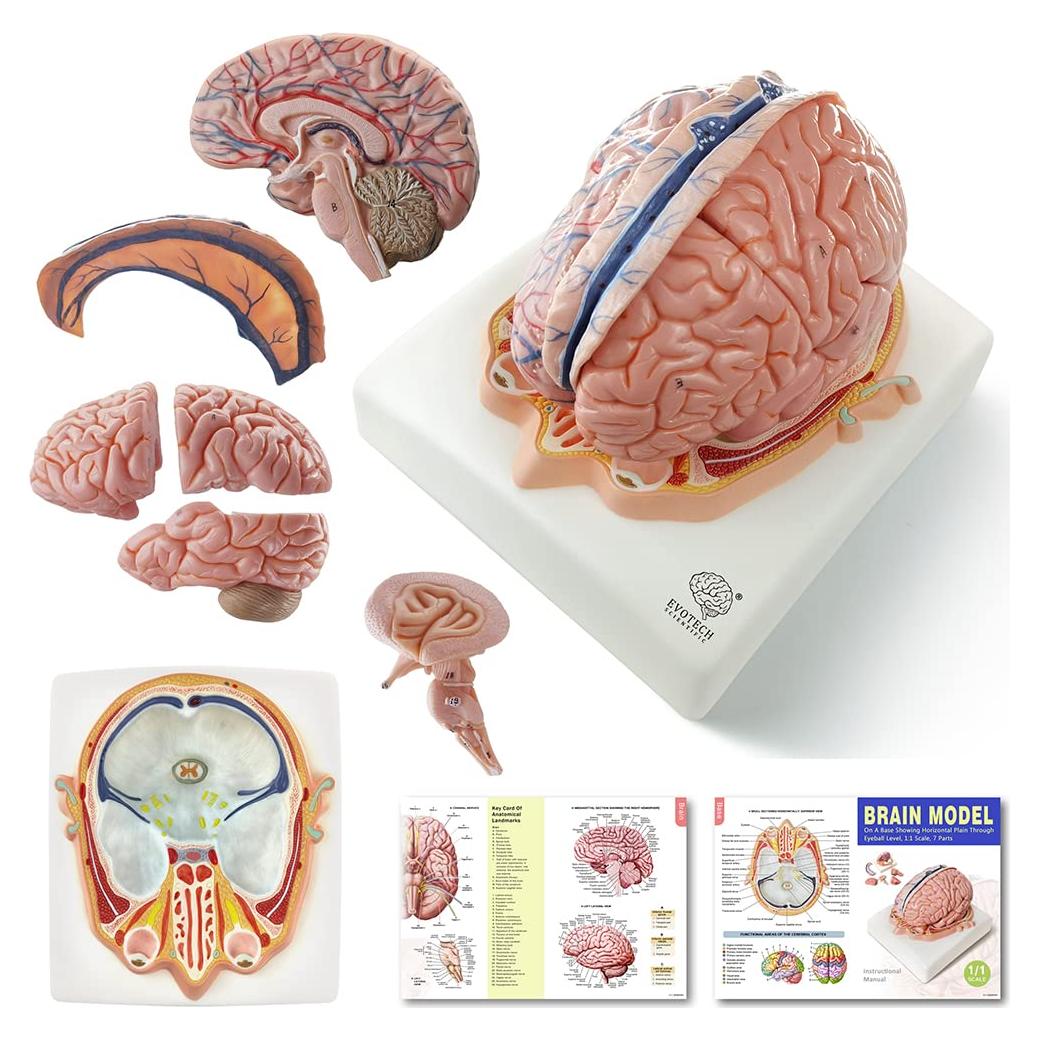

Modelos Anatómicos 3D EVOTECH SCIENTIFIC - Cuerpo, Corazón y Esqueleto